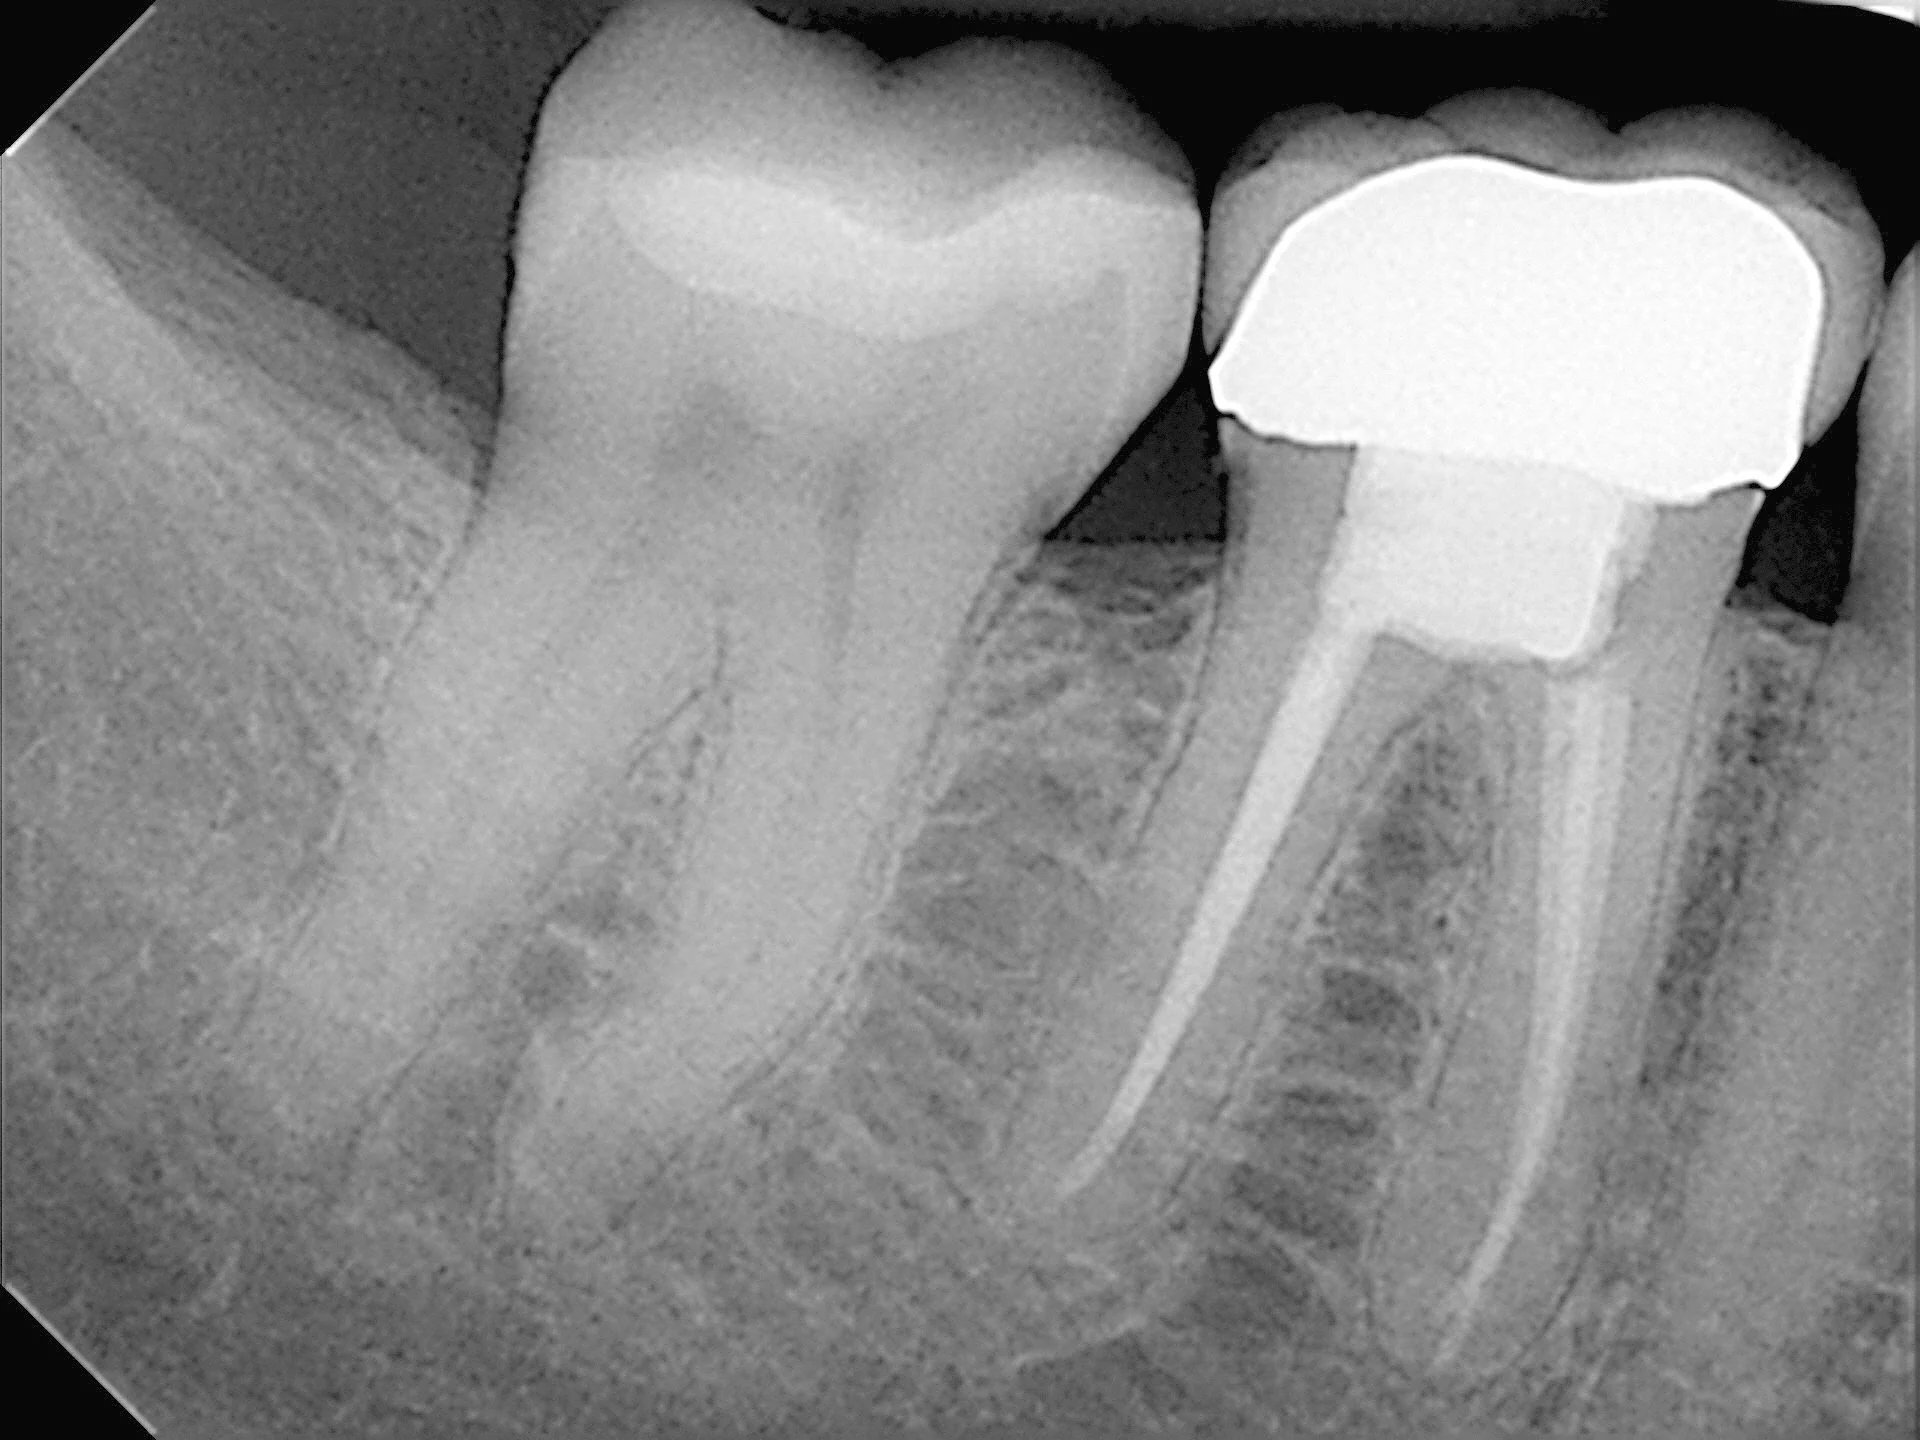

Dental X-ray showing a molar with a cavity, a tooth with a crown, and adjacent teeth.

Dental X-ray showing three molar teeth, with a root canal treatment visible on the first molar.

The procedure involves removing the pulp (the tissue inside the tooth), cleaning and disinfecting root canals and then filling and sealing it.